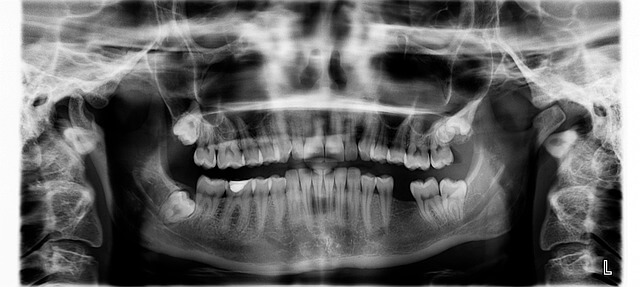

부정교합이 심하면 턱의 위치 자체가 틀어진 경우가 있습니다. 이때는 단순 교정으로 해결되지 않아 복합 치료가 필요해요. 하지만 무조건 큰 시술로 가기보다 정확한 진단이 우선입니다. 처음 진단받을 때 찍은 3D CT 영상 덕분에 제 문제는 ‘심각한 턱 틀어짐이 아님’을 알 수 있었죠. 그래서 단계별 치료를 선택했습니다. 부정교합 상태라도 정밀 검사를 통해 가장 덜 부담스러운 접근이 가능합니다.